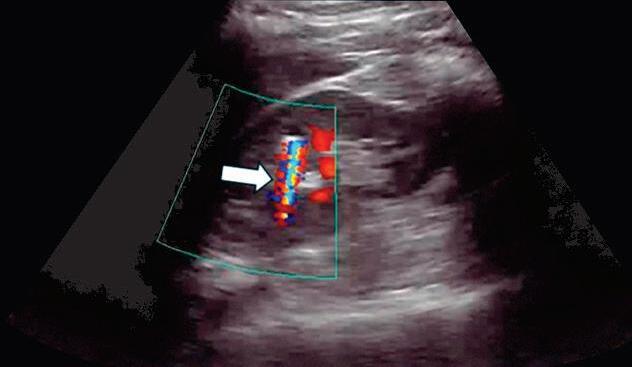

Fig. 2-47. “Artefato cintilante” no Doppler posterior ao cálculo.